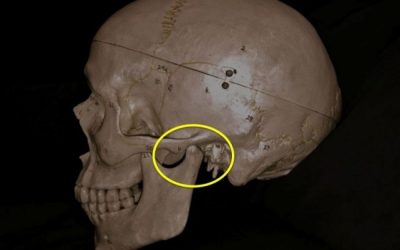

Las glándulas salivares, también denominadas salivales son distintas en su aspecto y su funcionamiento. Se dividen en glándulas mayores o principales (parótida, submaxilar y sublingual) y menores o accesorias. Sus conductos excretores desembocan en la mucosa de la boca y sus secreciones combinadas producen la saliva.

Tanto las mayores como las menores pueden ser el asiento de diversas lesiones tumorales, infecciosas, traumáticas… etc. que pueden requerir procedimientos quirúrgicos para su tratamiento.